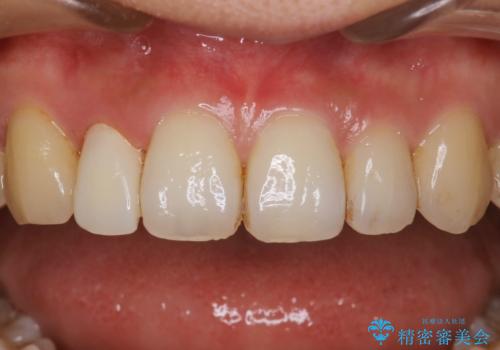

- 治療計画

- インビザラインで矯正中の患者様です。リファインメントのタイミングでホームホワイトニングをご希望でしたが、歯の表面にステインがかなり付着していたため、エアフローでのクリーニングからお勧めしました。

歯の表面にステインやバイオフィルムが付着していると、歯面がざらつき更に汚れが付きやすくなるだけでなく、付着物の影響でホワイトニング薬剤の浸透が悪くなりトーンアップ効果が減少します。歯の表面の汚れを落とすことで歯面もツルツルになり、ホワイトニングを行わなくても歯が白くなった様に感じられる場合もあります。

エアフローだけで歯が白くなったと喜んでいらっしゃいました。新しいマウスピースが届くまでの間はホームホワイトニングを行い歯の内部から白くしていきます。